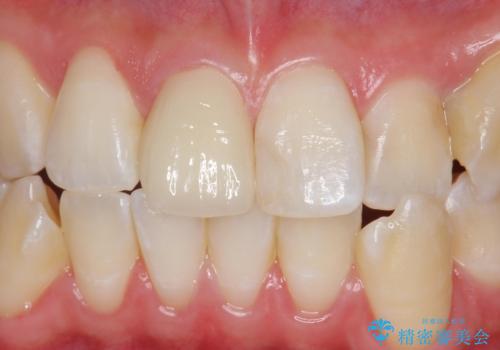

Dr. 岡田康成の症例写真

担当医 岡田康成<2025年4月10日更新>